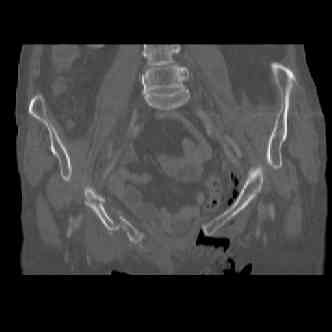

attached are several CT cuts. please let me know if you need more. the CT is pre-pelvic ex-fix placement.

Thank you.

injuries are limited to the pelvis. left rami open and visible in a 10cm vertical laceration just lateral to left labia majora. wound is grossly clean. no vaginal and no urinary issues. CT scan shows widening of both SI joints anteriorly but I think this is vertically stable pattern.

so the question is what next operatively if anything? concerns are infection, nonunion anteriorly and possible incompetence of the pelvic floor which may lead to prolapse issues. right rami are comminuted and plating may entail ilioinguinal approach to extend plate laterally to right iliac wing. retrograde screw up right rami is an option but I am not convinced it will add much. adding SI screws very doable, but major concern is restoring anterior ring. so far wound is clean and closed over a drain, and I have no plans to open it back up and wash again.

I wouldn't plate the front.

But I would add screws posteriorly.